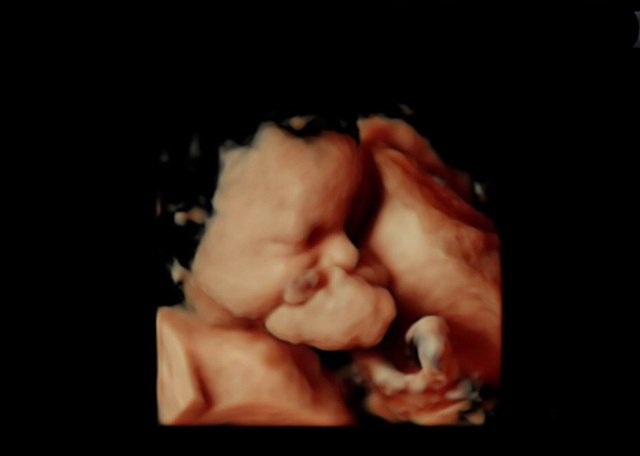

La intervención se planteó tras detectar en la semana 30 de gestación que el feto presentaba una gran tumoración dependiente del maxilar superior, y después de un seguimiento exhaustivo de su evolución, realizada por un equipo multidisciplinar, que en la semana 34 aconsejó la finalización del embarazo.

El procedimiento EXIT, fruto de la introducción de técnicas avanzadas de diagnóstico prenatal, permite el nacimiento parcial de un feto mediante cesárea, sin seccionar el cordón umbilical, lo que posibilita realizar intervenciones quirúrgicas o procedimientos invasivos sobre el feto mientras se oxigena a través de la placenta materna.

El doctor Cubillana detalló que este tipo de operaciones "evitan que los fetos que padecen una tumoración facial, en la cavidad oral o en el cuello, mueran por asfixia en el momento del nacimiento debido a la obstrucción del tumor sobre las vías respiratorias."